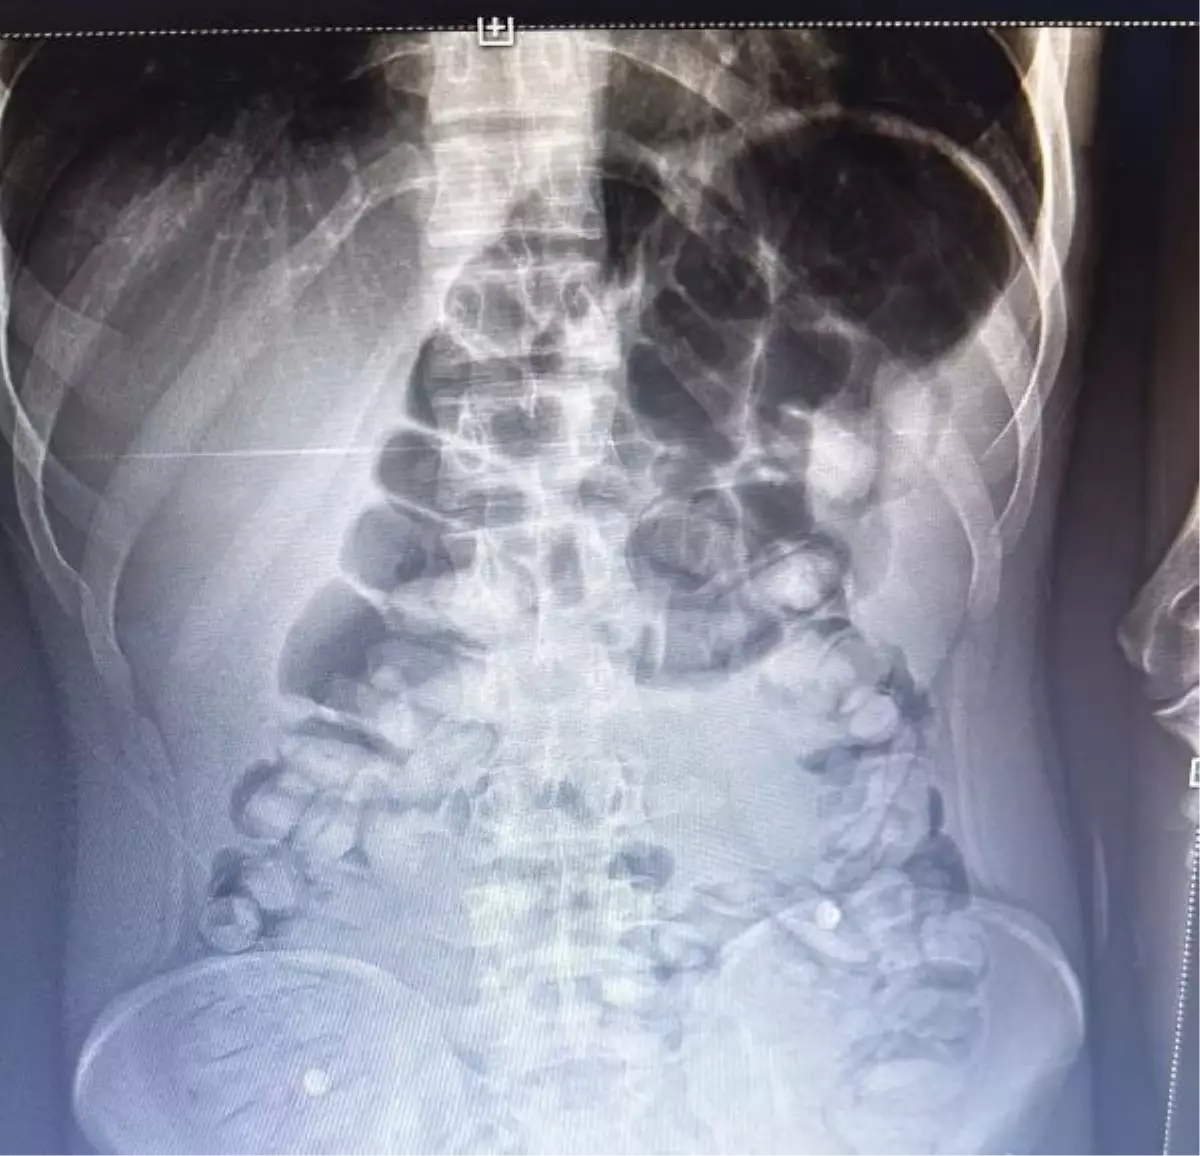

ERZURUM'da, yolcu otobüsünde şüphe üzerine hastanede röntgeni çekilen yolcunun midesinde Afyon sakızı, tespit edildi. Yolcu, midesindeki 1 kilo 134 gram Afyon sakızını doğal yollarla çıkardı.

İl Emniyet Müdürlüğü Narkotik Suçlarla Mücadele Şube Müdürlüğü ekipleri, bir yolcu otobüsünde yaptığı denetimde, durumundan şüphelendiği yolcuyu hastaneye götürdü. Burada rdöntgeni çekilen yolcunun midesinde uyuşturucu tespit edildi. İlaç verilen yolcu, 1 kilo 134 gram Afyon sakızını doğal yollarla çıkardı.